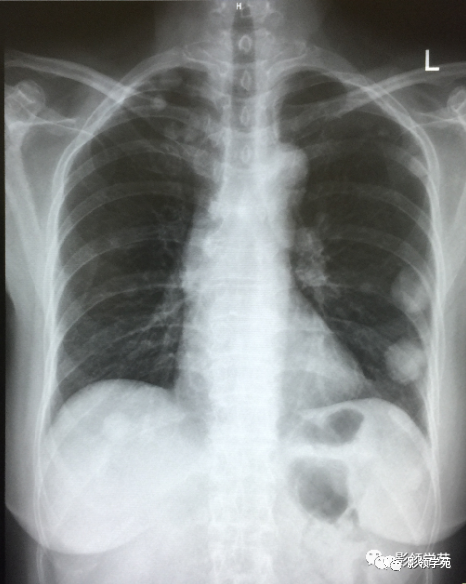

肿瘤外科患者,女55岁,9月前阴道不规则流血,诊刮术病检:子宫内膜浆液性腺癌(IV期),肺转移癌,盆腔淋巴结转移,骨转移,晚期无手术可能,省肿瘤TC方案化疗4周期,我院PAC方案化疗3疗程。

瘤外科患者,女,48岁,左乳癌根治术后2月术后化疗。病理:左乳伴髓样癌特征的乳腺浸润性导管癌。术后TAC方案化疗1个周期。

左乳切除术后,左肺下野两个大小不等高密度影。